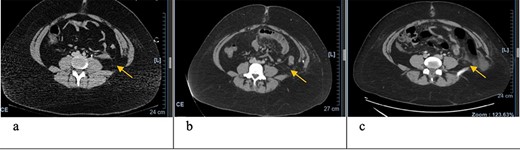

Axial CT scan with arrows pointing to internal and external oblique defects in June (a), August (b) and September (c); panel (a) shows rupture between internal and external oblique muscles at the attachment point of the quadratus lumborum; panel (b) shows fat stranding, suggesting inflammation of the epiploic appendage, and may be an early sign of delayed traumatic wall hernia; panel (c) shows herniation through the muscular defect.

In June, the patient’s CT imaging demonstrated a left posterolateral muscular defect of the fascia and external and internal obliques (Figs 1a and2a). Follow-up CT in August showed an increase in size with noticeable atrophy of the muscles with fat stranding (Figs 1b and2b). The atrophy may be due to the month-long period where she was immobile in the SICU. Muscle atrophy combined with the inciting event could be indicators for delayed TAWH, especially for those with prolonged hospital stays [3, 10]. When the hernia presented, CT imaging showed the appearance of fat and descending bowel (Figs 1c and 2c). We theorize that our patient’s MVC resulted in an initial defect or tear in the fascia, internal and external obliques. Her prolonged stay compounded the problem through muscle atrophy and peritoneal stretching. These factors, coupled with the activities of daily life, lead to the delayed presentation of traumatic lumbar hernia. Although lumbar hernias may rarely cause SBO, they may be indirectly linked.